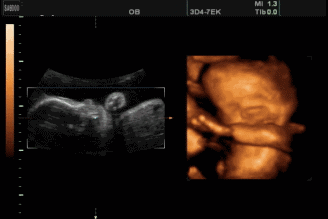

四维彩超可以直观、立体显示人体器官的三维结构及动态,实时地观察立体结构,所以准妈妈们还可以看到胎儿在母体内微笑、咬手、踢腿、伸懒腰、打哈欠的调皮可爱模样。